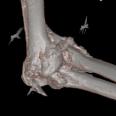

Die Orthopädie beschäftigt sich mit der Entstehung, Verhütung und Behandlung von angeborenen oder erworbenen Problemen des Bewegungsapparates. Die meist daraus resultierenden Lahmheiten werden bei uns umfassend abgeklärt. Hierbei kommen neben einer ausführlichen klinischen Lahmheitsuntersuchung auch weiterführende diagnostische Verfahren, wie Röntgen Computertomografie und Ultraschall zum Einsatz.